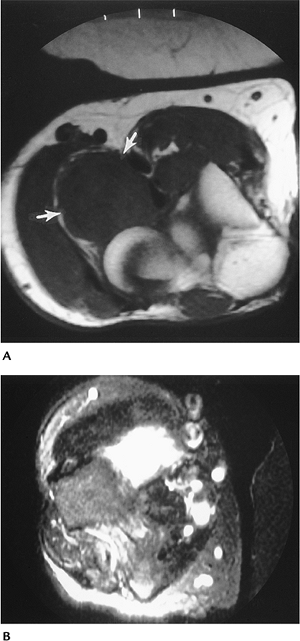

Soft Tissue Masses: Giant Cell Tumor of Tendon Sheath

Key Facts

-

Clinical:

Giant cell tumors of the tendon sheath

may be focal or diffuse. The localized lesion is most common in the

hand, usually the flexor tendons. Patients present with a slow-growing

soft tissue mass.

Age: 30 to 50 years

Sex: Females outnumber males.

Common locations: hand; less commonly, foot, knee, hip

Imaging features:

Radiographic features: soft tissue mass. Bone erosion in 15%.

CT: Soft tissue mass associated with tendon. Bone involvement easily appreciated.

MRI: Mass associated with a tendon and

low intensity (muscle density) on T1-weighted and intermediate to low

intensity on T2-weighted sequences. Irregular enhancement with

gadolinium.

Differential diagnosis:

Granuloma

Fibroma

Treatment: resection. Recurrence occurs in up to 20%.

P.735

P.736

![]() |

|

FIGURE 10-55 Giant cell tumor of the tendon sheath. AP (A) and lateral (B) radiographs demonstrate a soft tissue mass (open arrows) with bone erosion (arrowheads). Sagittal T2-weighted (C) image shows intermediate and low signal intensity with bone erosion. There is irregular enhancement (D) after contrast.